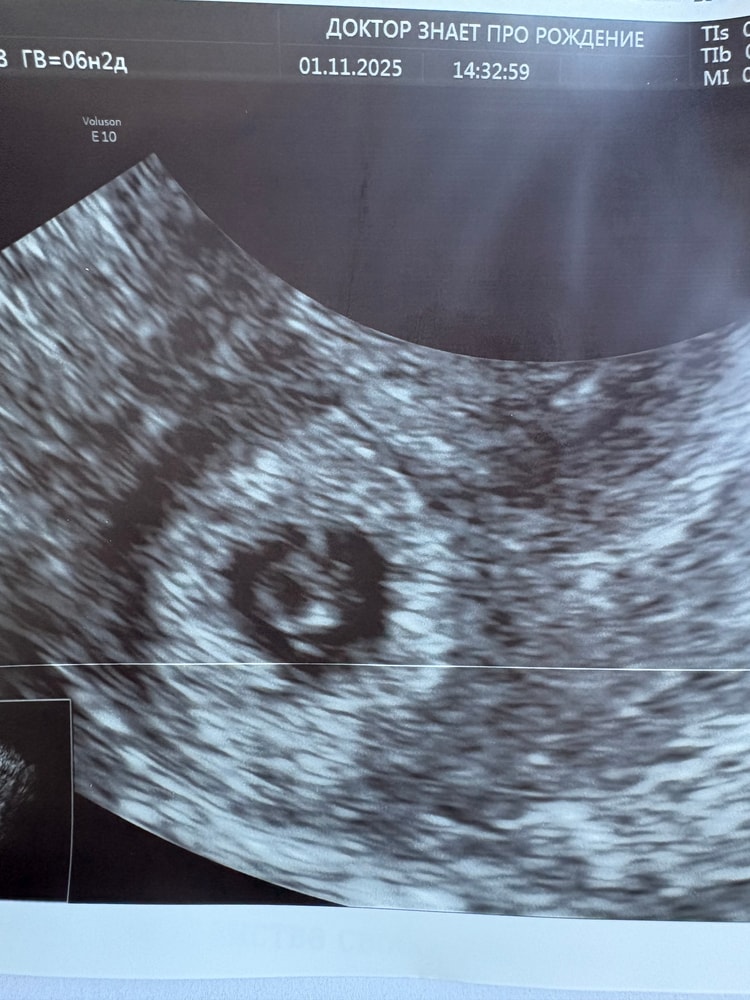

Результаты УЗИСегодня впервые услышала сердечко нашего малыша 🥹

ПЯ 13,8 мм, КТР 2,8 мм, желточный мешочек 4,9 мм, ЧСС 117 ❤️